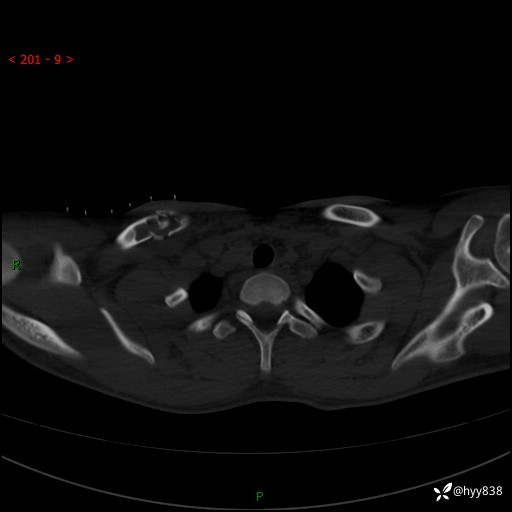

CT